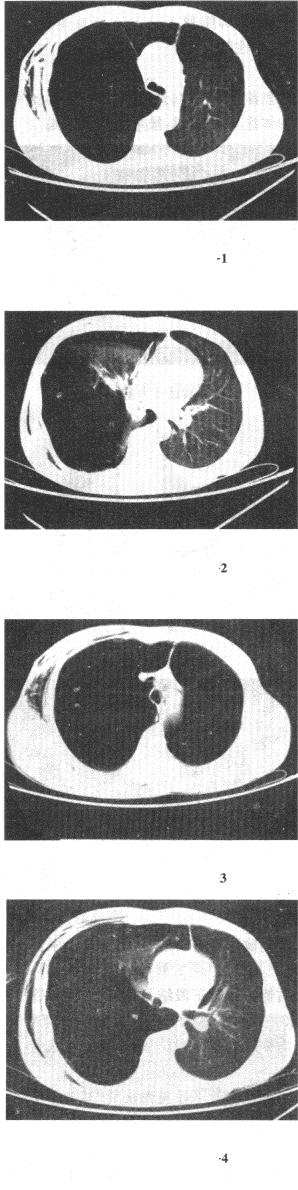

5岁男性,有不洁饮食史,自觉胸痛,气急,咳果酱色黏痰,CT示肺内多发边缘模糊斑片状影,内有多个空洞,空洞壁厚薄不均,部分空洞内有条状高密度影,最可能的诊断是() 过敏性肺炎。 急性肺脓肿。 肺吸虫病。 大叶性肺炎。 肺钩端螺旋体病。

患者男,32岁,被车撞伤后1个小时急诊行CT检查。结合图像,最可能的诊断为()